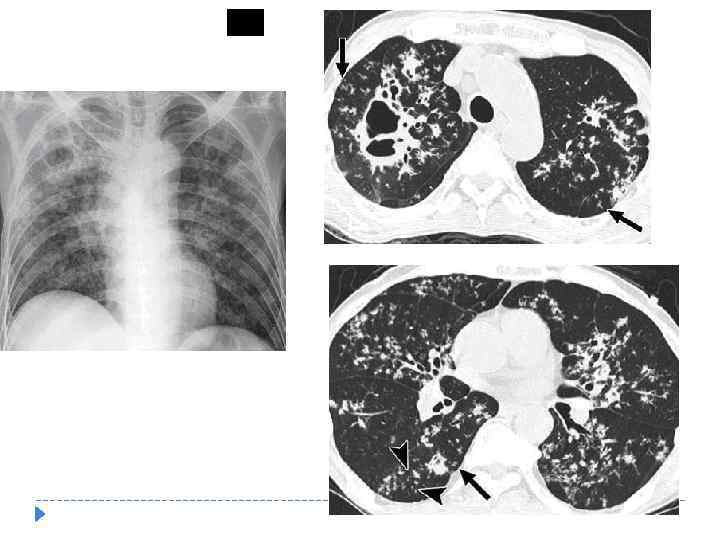

ЦИРРОТИЧЕСКИЙ ТУБЕРКУЛЕЗ ЛЕГКИХ Характеризуется массивным разрастанием соединительной ткани в легких и плевре с наличием заживших и активных туберкулезных очагов. Для цирротического туберкулеза характерны «синдром ограниченного» , «синдром субтотального» и «синдром тотального затемнения» со смещением прилежащих органов в сторону поражения.

ЦИРРОТИЧЕСКИЙ ТУБЕРКУЛЕЗ ЛЕГКИХ Характеризуется массивным разрастанием соединительной ткани в легких и плевре с наличием заживших и активных туберкулезных очагов. Для цирротического туберкулеза характерны «синдром ограниченного» , «синдром субтотального» и «синдром тотального затемнения» со смещением прилежащих органов в сторону поражения.